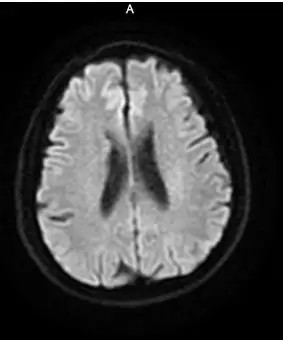

9:40分左右,患者逐渐开始出现烦躁、嗜睡,查体:言语不清,左侧肢体肌力0-1级,急查头颅MRI+MRA+颈部MRA阅片见,右侧基底节区急性脑梗死,右侧大脑中动脉闭塞。

头颅MRI+MRA(08-03日 11:50左右)

头颅MRI+MRA(2018-01-30日)